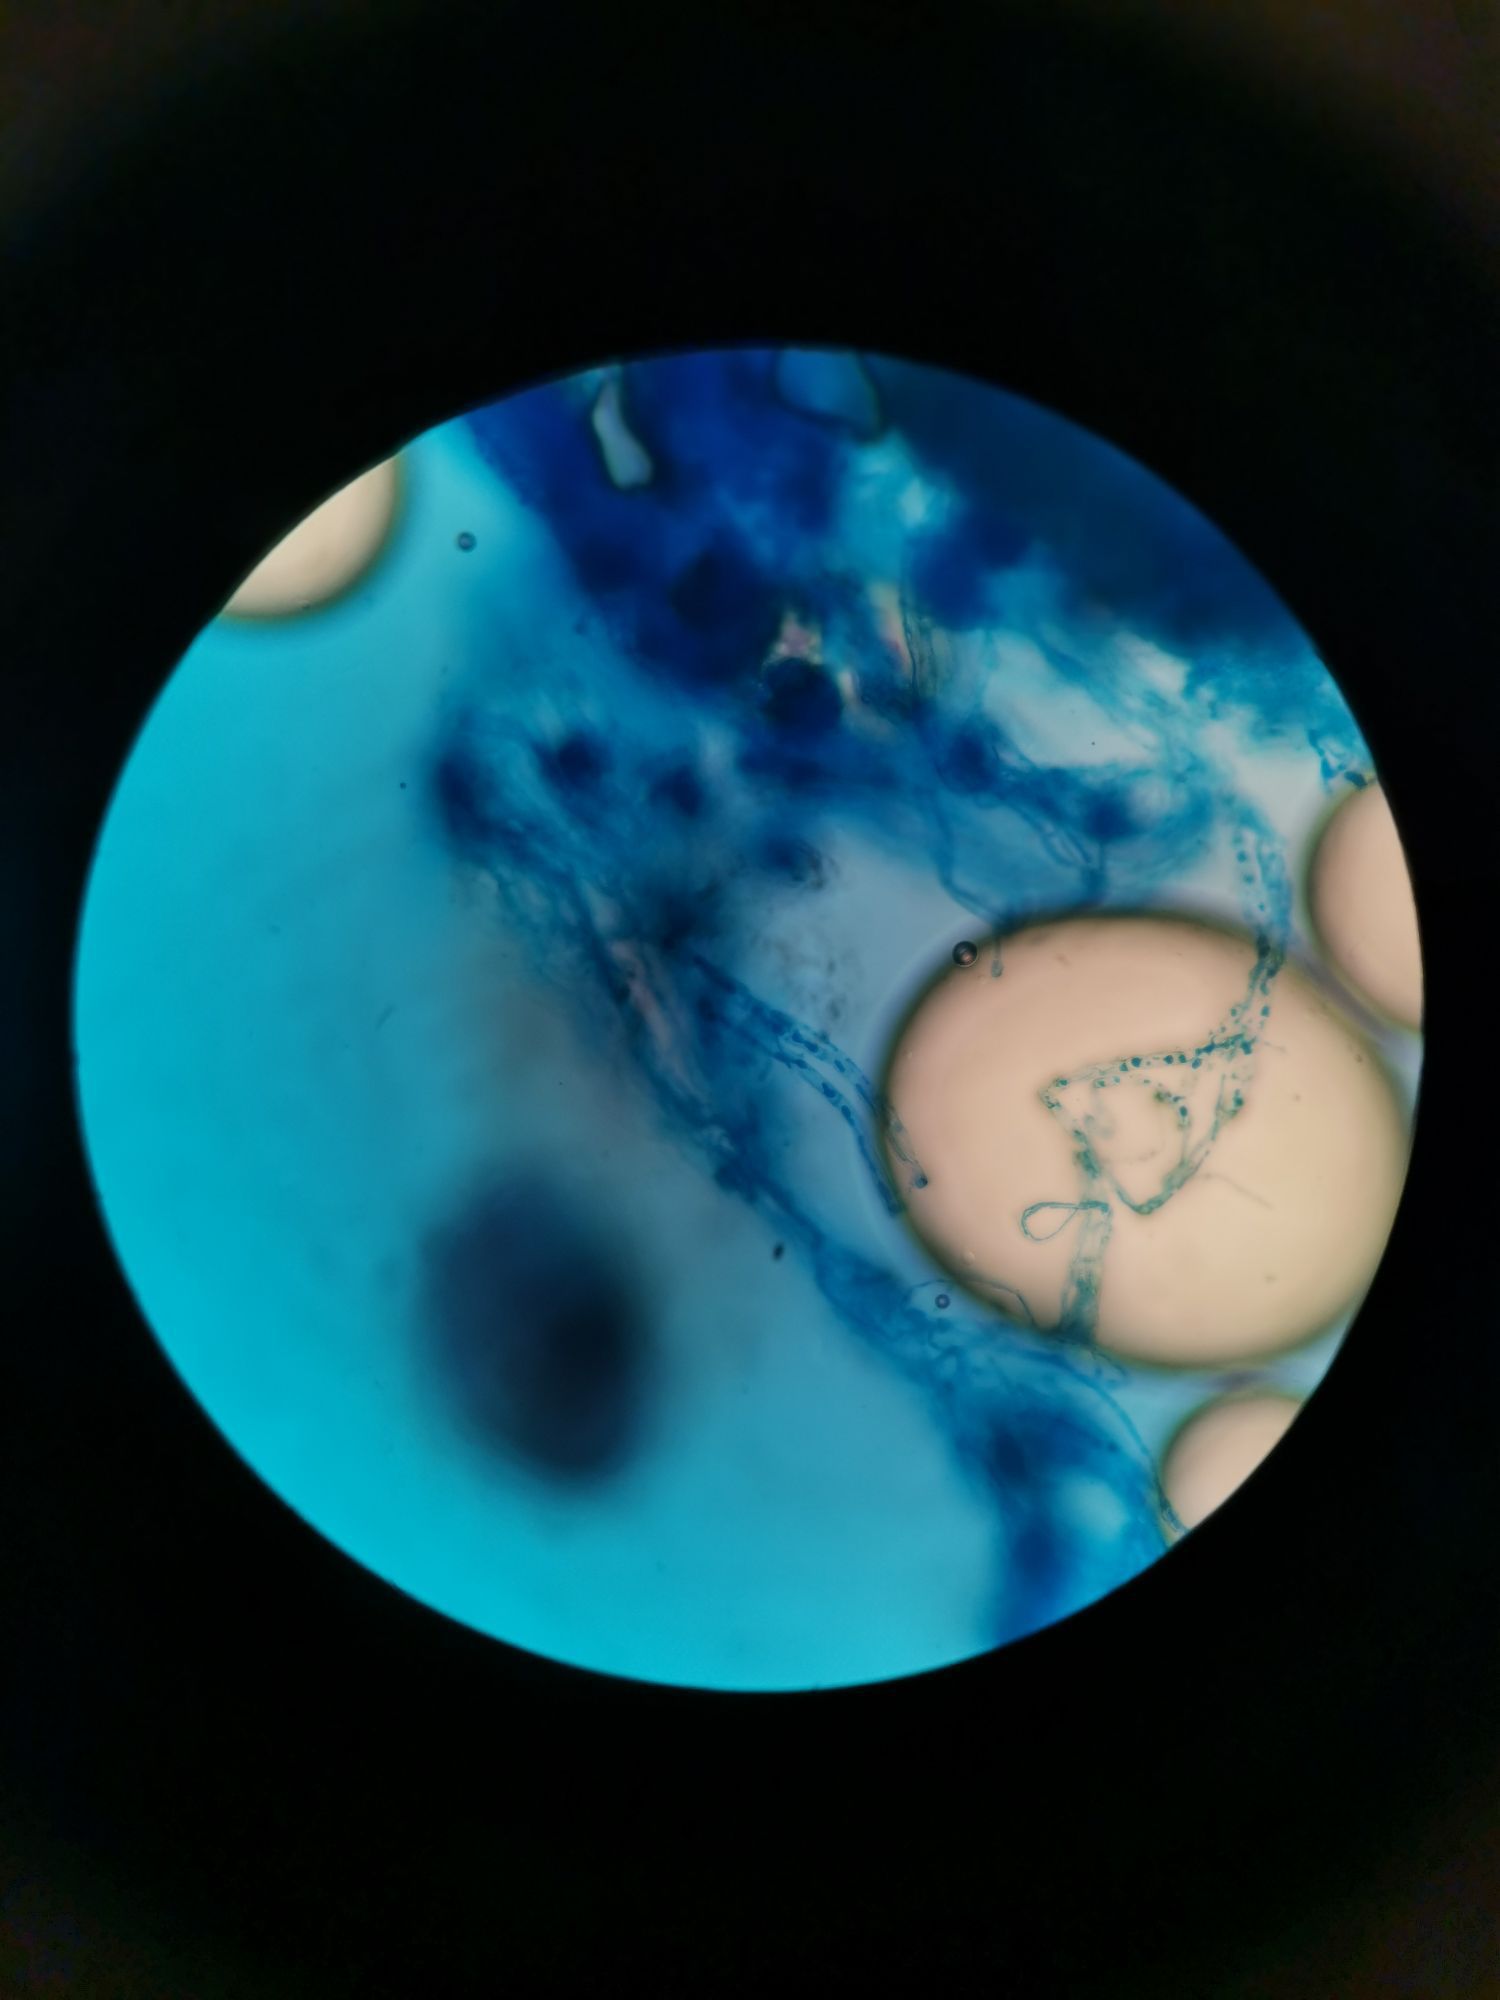

Which slide is this

Microbiology

Fungi